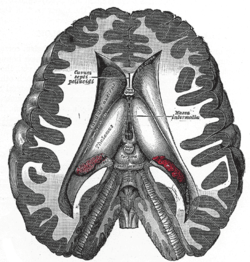

Transverse dissection showing the ventricles of the brain.